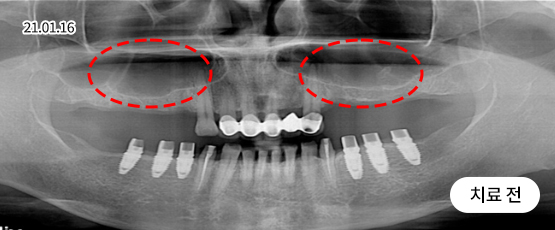

상악동 거상술

잇몸뼈가 없어도 만들어서 식립해 드립니다.

상악동은 윗 잇몸뼈 위쪽의 코 양옆으로 뻥 뚫려 있는 공간이며, 얇은 막으로 덮여 있습니다.

위쪽 어금니 임플란트를 심을 때, 이 부근의 잇몸뼈가 부족하면 임플란트가 상악동을 뚫고 들어갈 수 있습니다.

이를 방지하기 위해 상악동의 얇은 막을 들어 올리고 그 안에 잇몸뼈를 적당히 채워 주는 수술 방법이 상악동 거상술입니다.